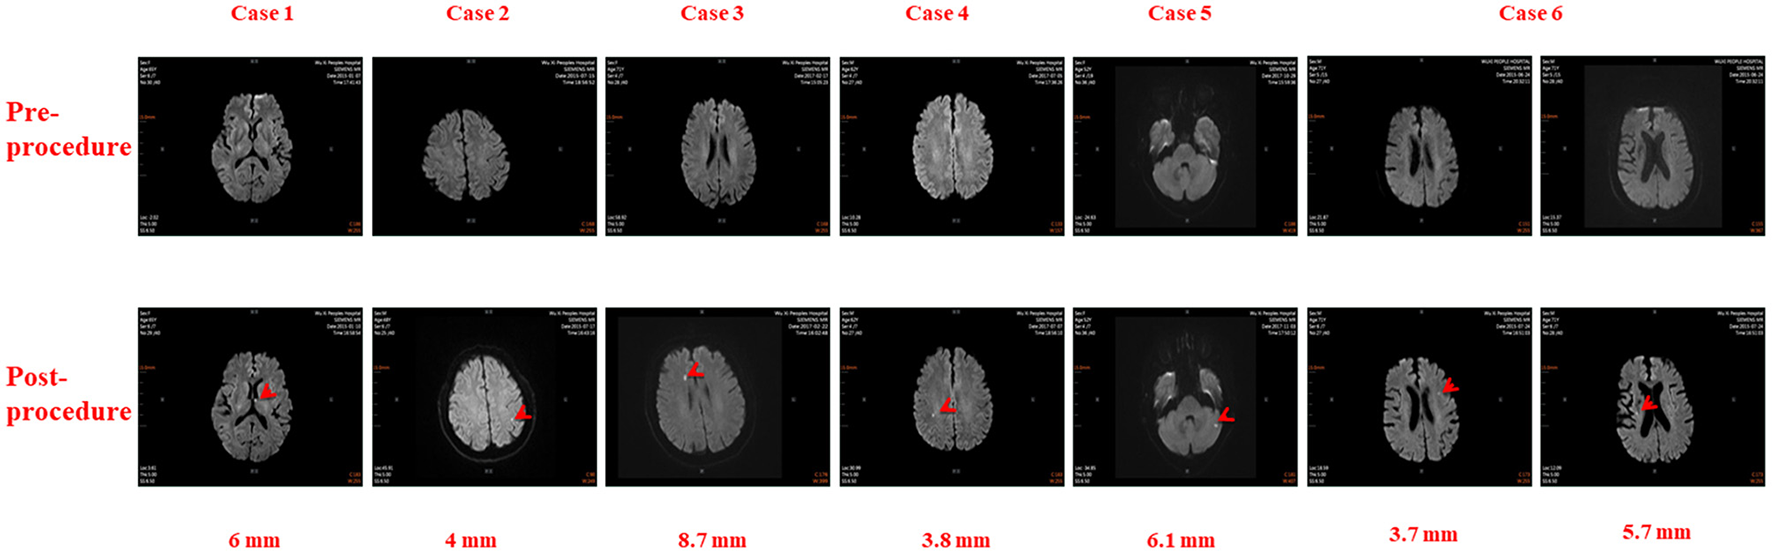

There were 26 total cases of SCE observed in this study, including 6 in the RMN group and 20 in the MC group. The incidences of SCE in the RMN group and MC group were 5.77 and 32.26%, respectively (X2 = 20.63 P < 0.001). The cerebral MRIs of SCEs in the 6 cases observed in the RMN group are shown in Figure 1, and the cerebral MRIs for the 20 cases of SCE in the MC group are provided in the Supplementary Data file.

Cerebral Magnetic Resonance Images in six patients before and after Atrial Fibrillation Ablation using Magnetic Navigation System: Case 1: Left thalamus (6 mm), Case 2: Left parietal lobe (4 mm), Case 3: Right frontal lobe (8.7 mm), Case 4: Right parietal lobe (3.8 mm), Case 5: Left cerebellum (6.1 mm), Case 6: Left frontal lobe (3.7 mm) and Right corona radiata (5.7 mm).